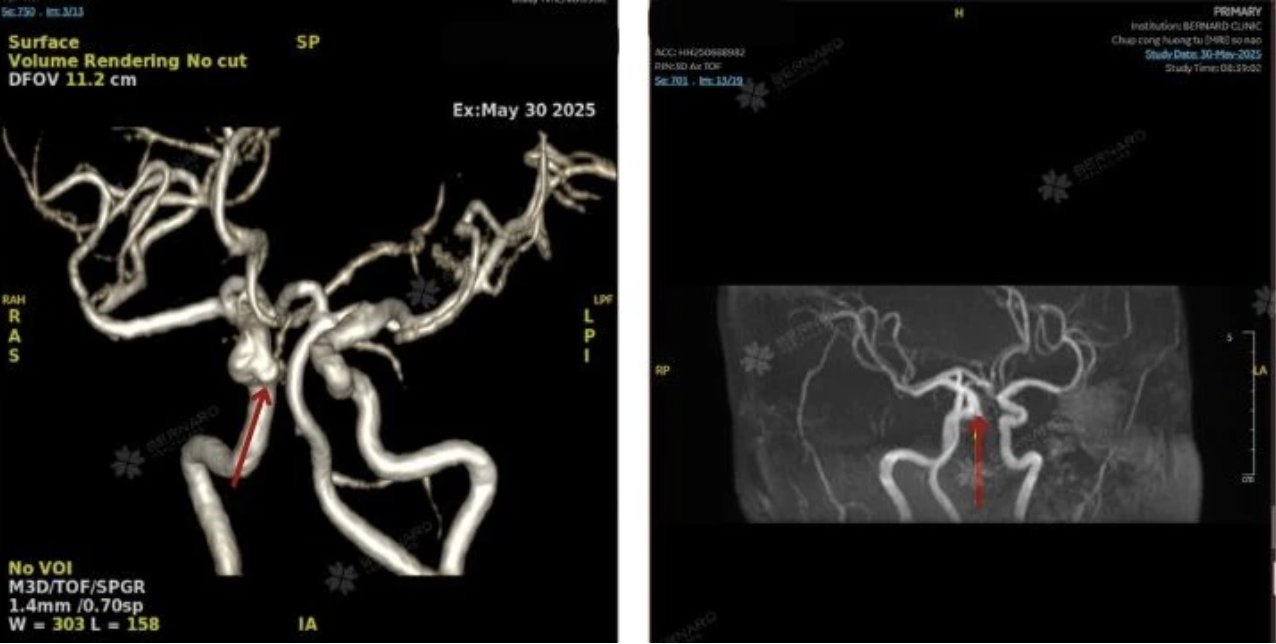

Kết quả MRI ghi nhận cùng lúc hai bất thường có ý nghĩa: túi phình động mạch cảnh trong phải kích thước khoảng 3 x 4 mm và u màng não có vôi hóa vùng trán phải, sát bản sọ. Cả hai tổn thương đều chưa gây triệu chứng nhưng tiềm ẩn rủi ro lớn nếu không theo dõi hoặc xử trí đúng thời điểm.

Kích thước túi phình của chị N. chưa vượt ngưỡng nguy hiểm, nhưng vị trí gần nền sọ khiến việc theo dõi và lựa chọn thời điểm can thiệp trở nên phức tạp hơn, tuyệt đối không thể chủ quan.